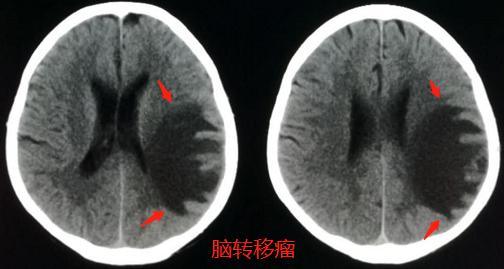

病例1,男性65,言语不清5天,怀疑脑血栓做了脑CT检查:

左顶叶巨大低密度水肿区,不按供血区分布,在脑灰白质交界区似乎有小结节,不符合脑梗死,首先考虑脑转移瘤。